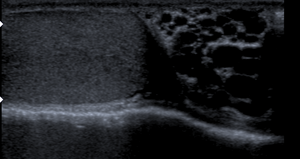

- إذا لم يتم التوصل لنتيجة بالفحص السريري يتم عمل سونار للخصية.

4– في الحالات التي يتم تشخيص الدوالي فقط عن طريق السونار ولا يتم تشخيصا بالفحص السريري يفضل عدم اجراء الجراحة لأن السونار ليس دقيق في هذة الحالات.